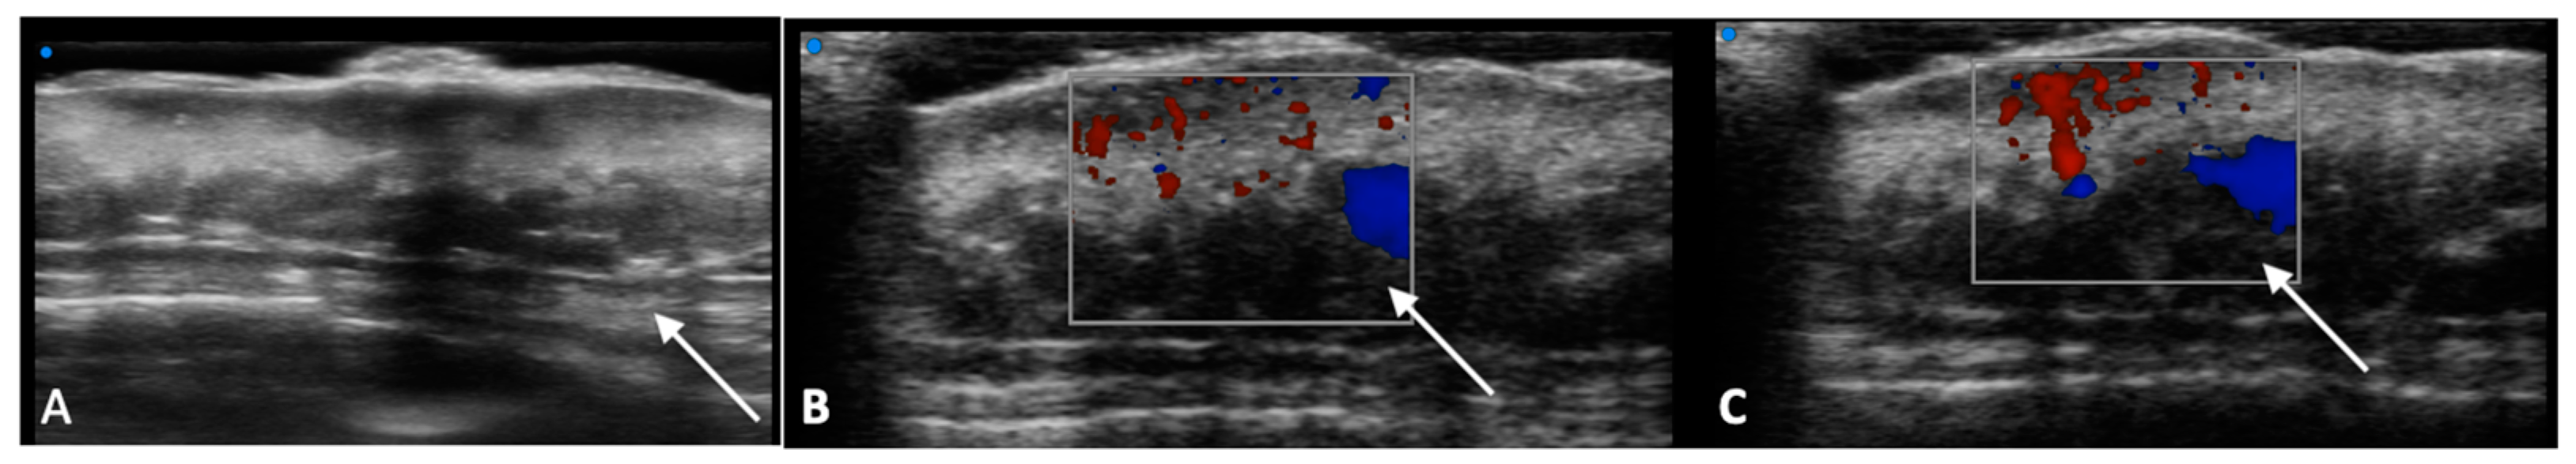

- Reginelli, A.; Belfiore, M.P.; Russo, A.; Turriziani, F.; Moscarella, E.; Troiani, T.; Brancaccio, G.; Ronchi, A.; Giunta, E.F.; Sica, A.; et al. A Preliminary Study for Quantitative Assessment with HFUS (High- Frequency Ultrasound) of Nodular Skin Melanoma Breslow Thickness in Adults Before Surgery: Interdisciplinary Team Experience. Curr. Radiopharm. 2020, 13, 48–55. [Google Scholar] [CrossRef]

- Belfiore, M.P.; Reginelli, A.; Russo, A.; Russo, G.M.; Rocco, M.P.; Moscarella, E.; Ferrante, M.; Sica, A.; Grassi, R.; Cappabianca, S. Usefulness of High-Frequency Ultrasonography in the Diagnosis of Melanoma: Mini Review. Front. Oncol. 2021, 11, 673026. [Google Scholar] [CrossRef]